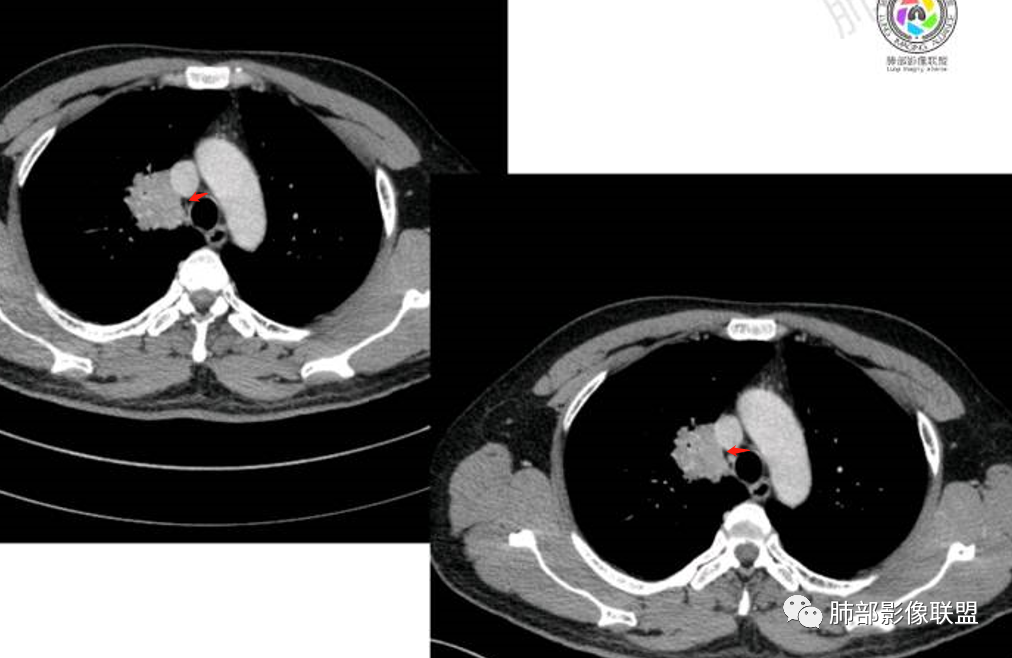

病理结果

病理结果:MALT

肺内黏膜相关淋巴组织淋巴瘤(MALT)

③扩张的充气支气管为其较特征性的表现,出现率约为89%,支气管管壁无破坏,支气管常扩张并达病灶的边缘,这与炎症性肺癌明显不同,其病理学基础是肿瘤起源于肺间质,肿瘤细胞沿着脏器解剖结构生长,周围增生的结缔组织牵拉导致支气管扩张,因而这类支气管扩张在肿瘤治疗后有时可消失;

④血管造影征是另一 点,强化的肺血管形态及走行正常,无扭曲或增 粗,其病理学基础为肿瘤细胞沿间质增生浸润,不破坏血管或支气管,病灶内肺支架结构完整,本研究发现率为75%;

⑤病灶多为中度强化,部分轻度强化;